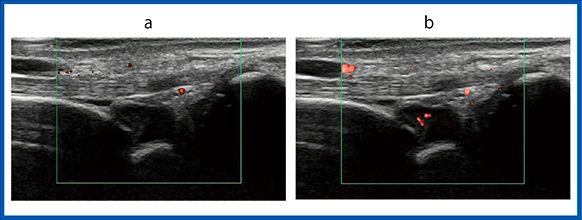

症例1は,左手第3指MCP関節の滑膜炎である。パワードプラ画像とSMI画像共に血流信号が豊富に描出されている(図2)。パワードプラ画像は血流信号が多く描出されているようにも見えるが,これはブルーミングによって血管からはみ出したものである。一方,SMI画像は血管の走行をきれいに描出している。

図2 症例1:左手第3指MCP関節の滑膜炎

a:パワードプラ画像 b:SMI画像